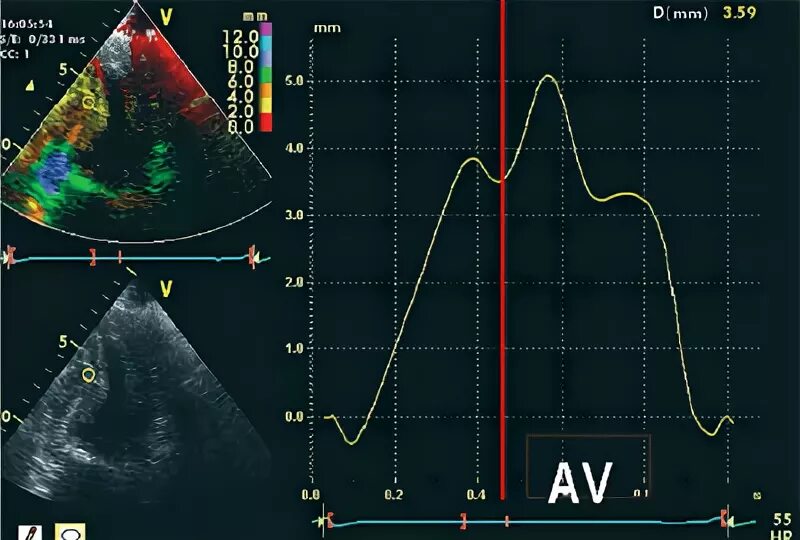

Гипокинез передних сегментов